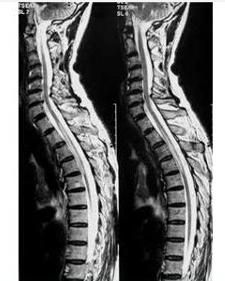

本病的確切病因尚未明了。脊髓炎大多為病毒感染所引起的自身免疫反應,或因中毒、過敏等原因所致的脊髓炎症。其病原主要有流感病毒、帶狀皰疹病毒、狂犬病毒、脊髓灰質炎病毒等,近年來有由肝炎病毒所導致脊髓炎的報告。尚有一部分患者原因不明,但病前常有某些上呼吸道感染的症狀。臨床上以橫斷性脊髓炎最為常見,其病變以胸段為主,其次為頸段,腰段及骶段病變較為少見。表現為脊髓病變水平以下的肢體癱瘓、感覺缺失和膀胱、直腸功能障礙。

病理改變為炎症和變性,主要表現為軟脊膜和脊髓水腫、變性、炎症細胞浸潤、滲出、神經細胞腫脹,嚴重者出現脊髓軟化、壞死、出血,慢性期神經細胞萎縮,神經髓鞘脫失、軸突變性,神經膠質細胞增生。本病急性期腦脊液檢查可有白細胞數及蛋白含量輕度增高。